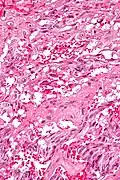

Very high mag.

Very high mag. -

Very high mag.

Very high mag.

A gangliocytic paraganglioma is a rare tumour that is typically found in the duodenum and consists of three components: (1) ganglion cells, (2) epithelioid cells (paraganglioma-like) and, (3) spindle cells (schwannoma-like).[1]

GP consist of three components (1) ganglion cells, (2) epithelioid cells (neuroendocrine-like), and (3) spindle cells (schwannoma-like). The microscopic differential diagnosis includes poorly differentiated carcinoma, neuroendocrine tumour and paraganglioma.[1]